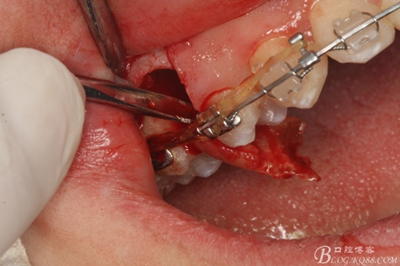

圖11.仔細(xì)考慮之后,在14頰側(cè)做垂直切口,切口長度僅達(dá)膜齦聯(lián)合處,做小切口。

圖12. 做垂直切口+齦溝內(nèi)切口,形成角形瓣,暴露出15根面。